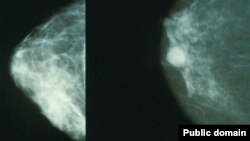

Акси рентгени синаи сиҳҳат (аз чап) ва гирифтори саратон (аз рост)